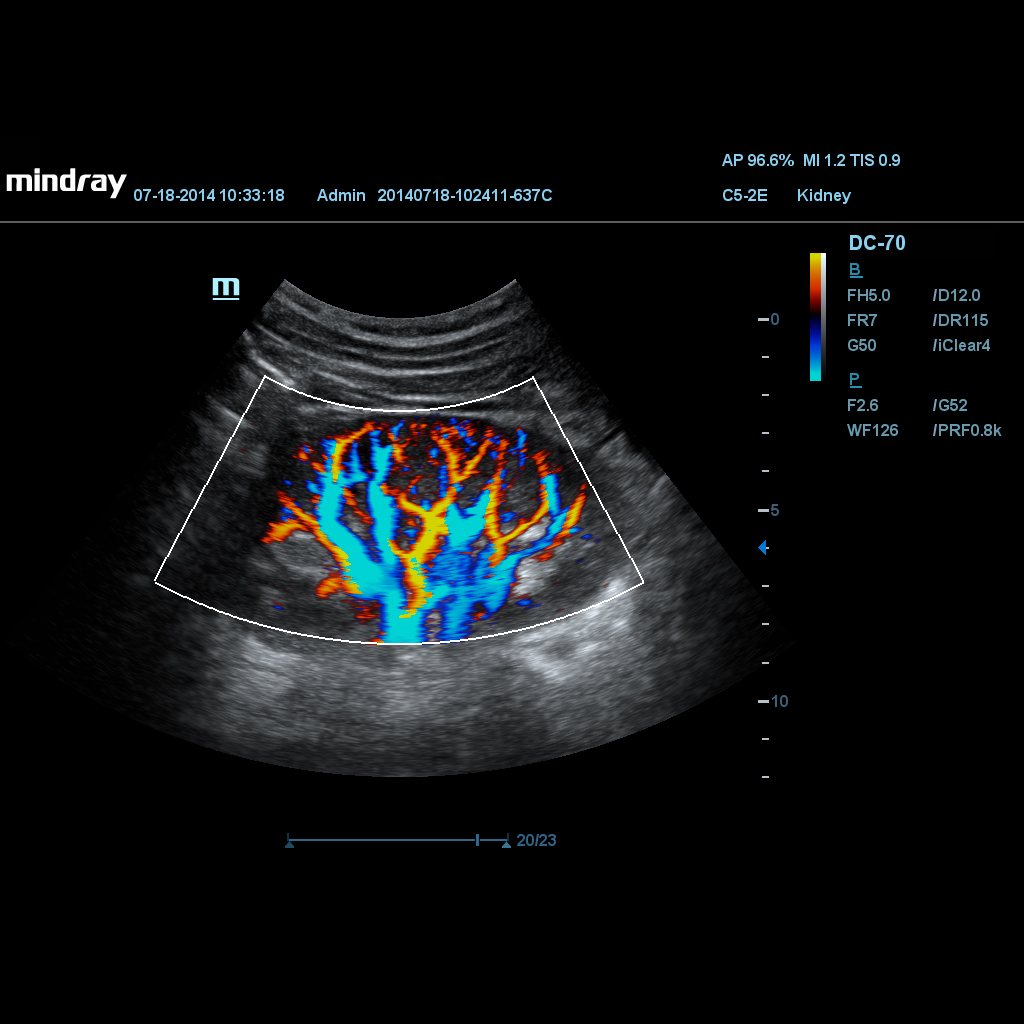

Специализиран режим за Цветен и Мощностен доплер с много висока чувствителност, за визуализиране на малки съдове и слаби кръвотоци, дава повече диагностични детайли и по-малко алайзинг.